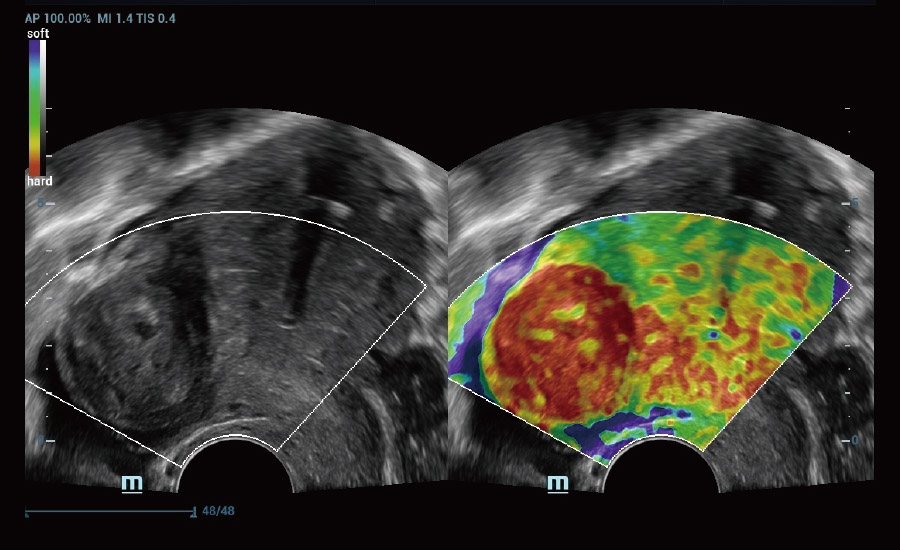

Scenario-oriented Full-stack Intelligence

Combining advanced algorithms and domain-specific knowledge, the innovative Smart Scene solution enables auto identification of tissue characteristics and provides organ-specific diagnosis with full-stack intelligence. Based on auto scenario identification, the solution not only realizes smart 2D scanning with auto settings and measurements, but also delivers 3D full-stack intelligence in every step from volume imaging optimization to the difficult 2D plane acquisition, and quantification throughout whole procedure. It helps a lot in reducing the dependency on clinical skills, while increasing diagnostic accuracy, confidence and efficiency.